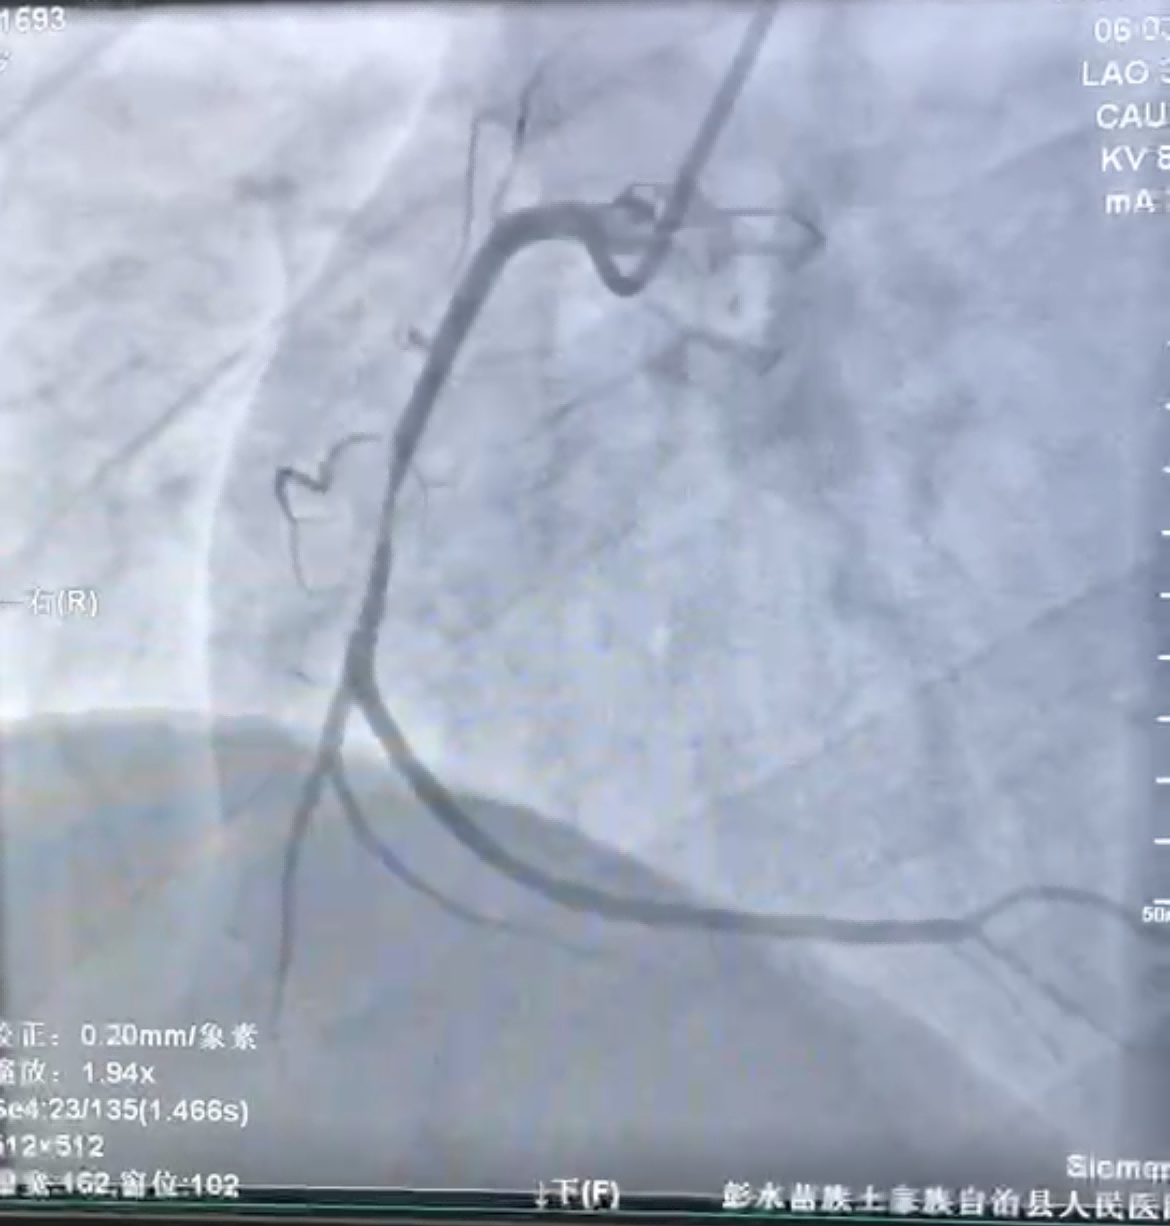

47岁的谢先生因胸痛半月,再发加重3小时,到河豚直播体育app就诊,急诊科张波医师立即行心电图等检查后,考虑急性心肌梗死,经心内科吴玉兰主治医师会诊后立即启动胸痛中心绿色通道,与患者及家属沟通后行急诊冠状动脉介入治疗。通过冠脉造影检查,患者右冠中段次全闭塞,可见血栓影(见图1)。

(图1)